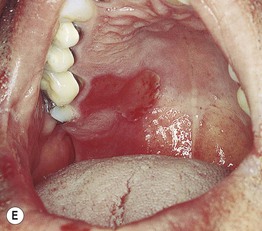

Fig. 17.11 Fixed drug eruptions (FDE). Well-demarcated erythematous (A) to violet-brown plaques that can develop a detached epidermis (B), bulla (C), or erosion (D, E) centrally. As lesions heal, circular or oval areas of hyperpigmentation are commonly seen (F). Responsible drugs were phenolphthalein (A), naproxen (B), ciprofloxacin (D), allopurinol (E), and trimethoprim–sulfamethoxazole (F). C, Courtesy, Jean Revuz, MD; D, E, Courtesy, Kalman Watsky, MD; F, Courtesy, Mary Stone, MD.